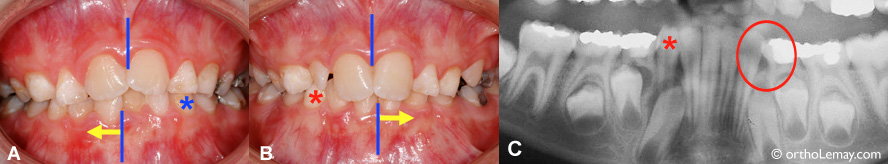

Arcade supérieure : La perte de la canine temporaire droite a causé une migration des incisives vers la droite (flèche) et une perte d’espace (cercle) qui empêchera l’éruption normale de la canine permanente (voir radiographie).

Arcade inférieure : La perte de la canine et première molaire temporaires du côté gauche ont permis aux incisives inférieures de se déplacer vers ce côté (flèche), causant un manque d’espace (cercle) pour la sortie des autres dents (voir radiographie).

La ligne médiane est indiquée par le pointillé jaune. Idéalement le contact entre les incisives supérieures et inférieures serait aligné avec cette ligne. On peut cependant bien voir que le haut est déplacé vers la droite (du patient) et le bas vers la gauche.

Il est indiqué d’extraire les dents temporaires avec les losanges rouges (radiographie). Ceci accélèrera et redirigera les dents permanentes qui les remplaceront et peut aider à améliorer le mauvais alignement des lignes médianes… sans toutefois le “garantir”.